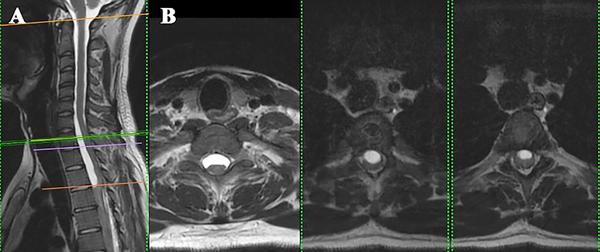

Se presenta el caso de una paciente de 21 años de edad, con antecedentes de infección por VIH, sífilis, consumo de drogas ilícitas y alcohol, que consulta por parestesias en ambos miembros inferiores de 6 meses de evolución, a lo que agrega paraparesia y dificultad en la marcha en los últimos 3 meses, con empeoramiento progresivo. Al examen físico presentaba una paraparesia moderada, hipertonía, hiperreflexia e hipoestesia en todas las modalidades sensitivas en miembros inferiores con nivel sensitivo T4 y signo de Babinski bilateral, así como también dolor dorsal con irradiación a ambos miembros inferiores. En la resonancia magnética (RMN) de columna completa se observaba una imagen a nivel T1 a T3, hipointensa en T1, hiperintensa en T2 y STIR, sin captación de contraste endovenoso, con desplazamiento posterior de la médula espinal y adelgazamiento de la misma (Figura 1 y 2). Se interpretó el cuadro como un quiste aracnoidal asociado a una aracnoiditis adhesiva. En este contexto, debido a la progresión y severidad de los síntomas, se realizó laminotomía T1-T2-T3 y evacuación de la lesión quística en el mismo nivel (Figura 3). Se enviaron muestras de aracnoides a anatomía patológica, la cual demostró “fragmento de tejido dural con fibroesclerosis y vasocongestión”; a su vez se realizaron cultivos de gérmenes comunes, hongos, parásitos, tuberculosis y PCRs virales, los cuales resultaron negativos.

Figura 2: RMN con corte sagital (A) y axiales a distintos niveles (B). Se observa el desplazamiento posterior de la médula espinal y el quiste anterior a la misma.